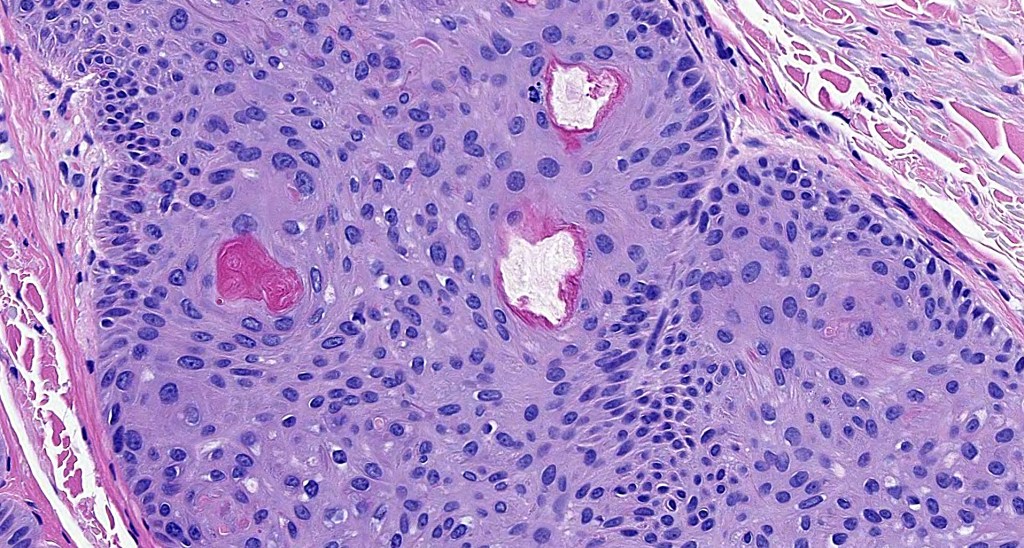

•PAS+ve cytoplasmic vacuolation indicating outer root sheath differentiation

•No pleomorphism or significant mitotic activity

•Eosinophilic basement membrane